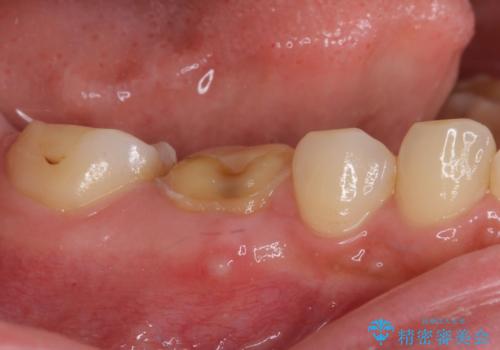

- 奥歯のクラウンが外れたままにしているとのことで来院された患者様です。

奥歯に特に症状はなかったのですが、排膿路が歯肉に認められたため、根管治療を行った上でオールセラミッククラウンにて補綴治療を行うこととしました。